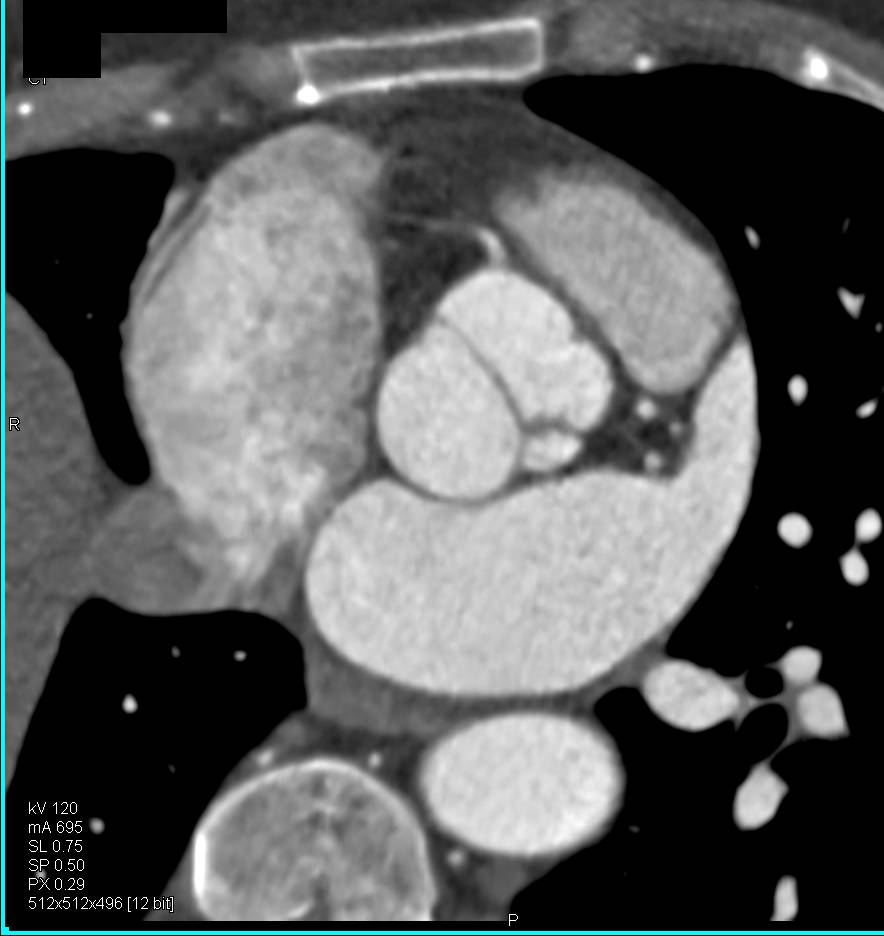

Ulcerating Breast Cancer with Axillary and Internal Mammary Nodes